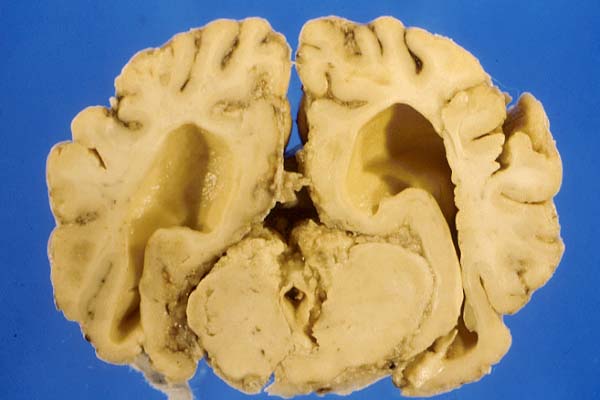

- Case 17-1. Gross Brain (see comments in text).

- Gross Pathology: The necropsy was performed at the

farm by the submitting veterinarian. Reportedly, no gross changes

were found in organs other than the brain. Gross examination

of the brain revealed increased cerebrospinal fluid (CSF), coning

of the cerebellum and flattening of cerebral gyri. The leptomeninges

were markedly thickened mainly over the cerebellum, base of the

cerebrum, and occipital cortex. The mesencephalic aqueduct was

blocked by cellular and fibrin exudate and dilation of lateral

ventricles (internal hydrocephalus). The fixed brain was sent

to our laboratory.